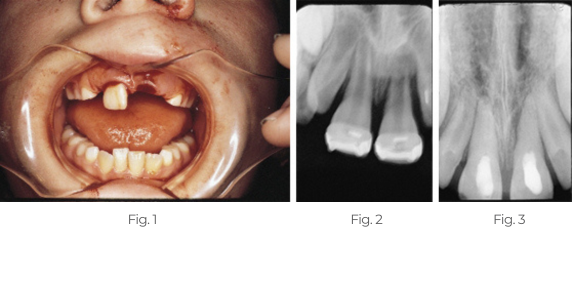

Behandlung eines abgerissenen Zahns

Dieses Kind stellte sich mit avulsierten linken zentralen und traumatisierten rechten zentralen Schneidezähnen vor. Zwei Wochen nach der Replantation und Schienung wurde die Pulpa entfernt und Pulpdent® Paste in die Wurzelkanäle eingebracht. Der Fall wurde 12 Monate lang regelmäßig beobachtet und die Pulpdent Paste wurde bei jedem Besuch gewechselt. Nach einem Jahr wurden die Wurzelkanäle mit dem Pulpdent® Root Canal Sealer unter Verwendung der Pressure Syringe-Technik obturiert.

Abb. 1: Das Foto zeigt ein Kind mit einem avulsierten linken zentralen und einem traumatisierten rechten zentralen Schneidezahn.

Abb. 2: Die Röntgenaufnahme zwei Wochen nach der Replantation zeigt den replantierten Zahn, offene Wurzelspitzen und Knochenverlust. Bei diesem Besuch wurden die Wurzelkanäle ausgehandelt und Pulpdent Paste als Verband aufgetragen, um die Heilung zu stimulieren und einer traumatischen Abstoßung vorzubeugen (nicht abgebildet).

Abb. 3: Die Röntgenaufnahme ein Jahr nach der Behandlung zeigt Pulpdent Paste in den Wurzelkanälen, Apexifizierung und Knochenauffüllung.